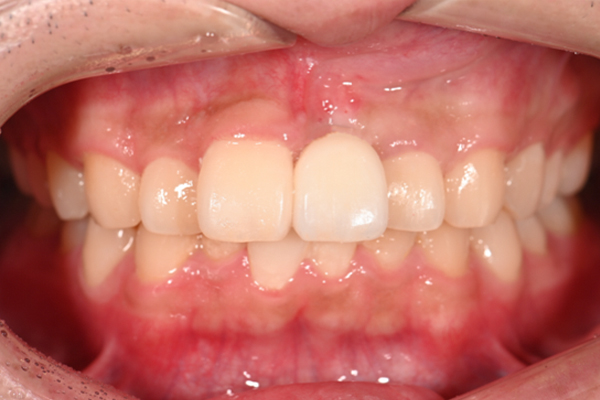

| 主訴 | 全体的にきれいにしたい |

|---|---|

| 治療内容 | 午前中に上下顎共に重度の歯周病、虫歯のため全ての歯を抜歯させていただき下顎はインプラントの土台を3本埋入し歯型を取り午後に上部構造(下顎全ての歯)を装着、上顎は一度総入れ歯を装着させていただきました。 治療が1日で完了しその日のうちに噛めるようになります。 |

| 治療期間 | 2回(1回目に資料取りをさせていただき2回目に下記の全ての治療をさせていただきました。) |

| 治療費 | 250万円 |

| 治療 リスク | 抜歯した部位などに関しては当日痛みが出ますので痛み止めなどを処方させていただきます |